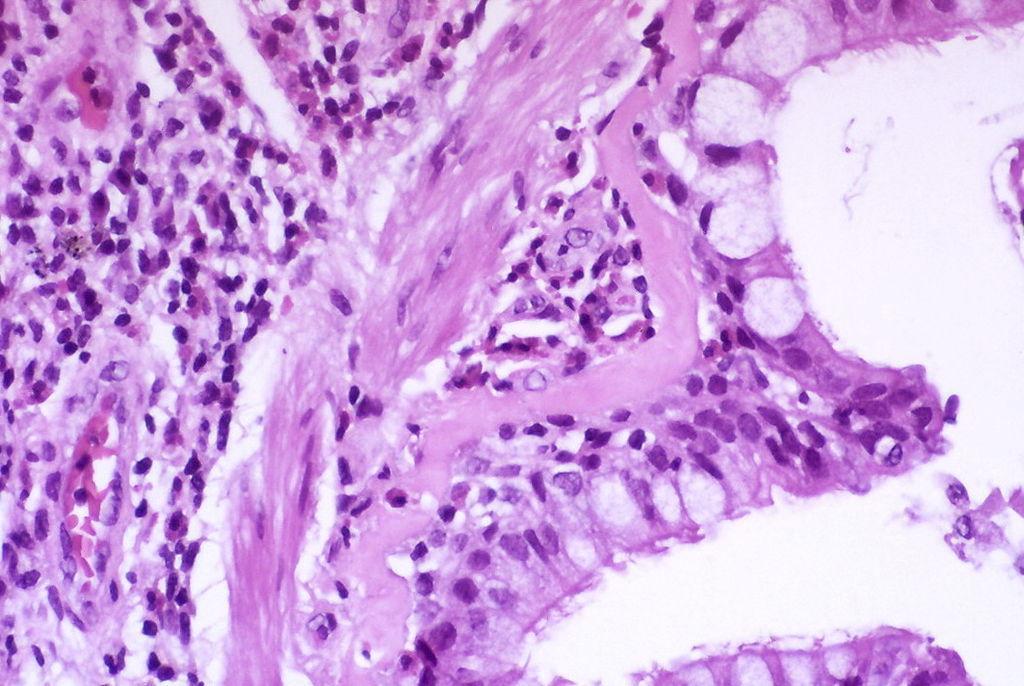

Asthma has been associated with a loss of balance between Th1 and Th2 responses. Altered Treg and Th17 responses have also been shown to be crucial in the onset of the condition. Th17 cells secrete IL-17 which is responsible for the regulation of pulmonary inflammation and Tregs secrete TGF-β and IL-10 which are also responsible for suppression of immune responses.

The mTOR pathway involves mTOR, a serine/threonine kinase which regulates cell growth and survival. PI3K also forms part of the pathway and phophorylates Akt which activates mTOR and another protein known as S6K1. A dysfunctional mTOR pathway has been linked to diseases such as cancer and systemic lupus erythematous. Since asthma is a disease that is caused by an immune imbalance, the authors hypothesized that the mTOR pathway was likely causing the Th1/Th2 imbalance seen in asthma patients and investigated whether inhibiting the mTOR pathway would suppress asthma onset.

The authors found that mTOR activation was significantly higher in patients who experienced asthma attacks as opposed to those who has pneumonia or healthy controls. Asthma patients had higher Il-17 and IL-4 levels when compared to the other groups but had lower regulatory (TGF-β, IL-10) and Th1 (IFN-γ) responses.